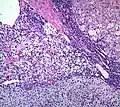

Histopathology

The microscopic histopathology analysis of the tissue samples obtained from the adrenal cortex of individuals presenting with adenoma-associated symptoms such as primary aldestronism (PA) indicates that adenoma cells are relatively larger with different cytoplasm, and increased variation in nuclear size. This indication is based on comparison between the healthy (normal) and affected (adenoma-associated) adrenal cortex tissue samples.